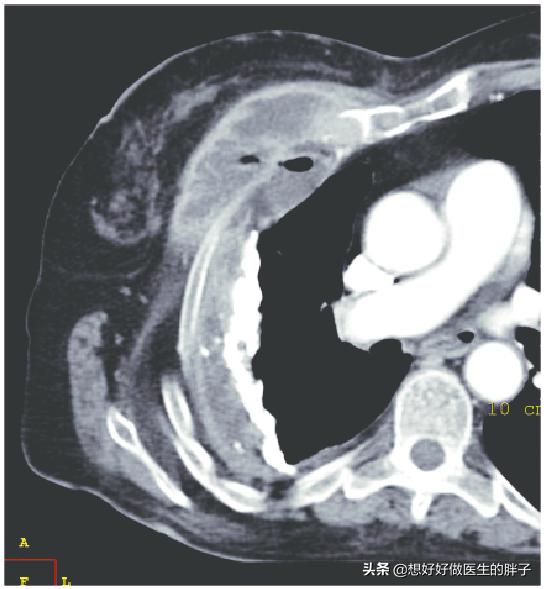

Un adénocarcinome in situ de 9 mm, qui ne présente aucun symptôme et dont toutes les fonctions corporelles sont normales, ne peut être détecté qu'à un stade précoce par tomodensitométrie et a été enlevé chirurgicalement.

Sans ces dispositifs et en utilisant uniquement un stéthoscope, je crains que la maladie ne soit détectée que trois à cinq ans plus tard, lorsqu'elle aura atteint un stade avancé.